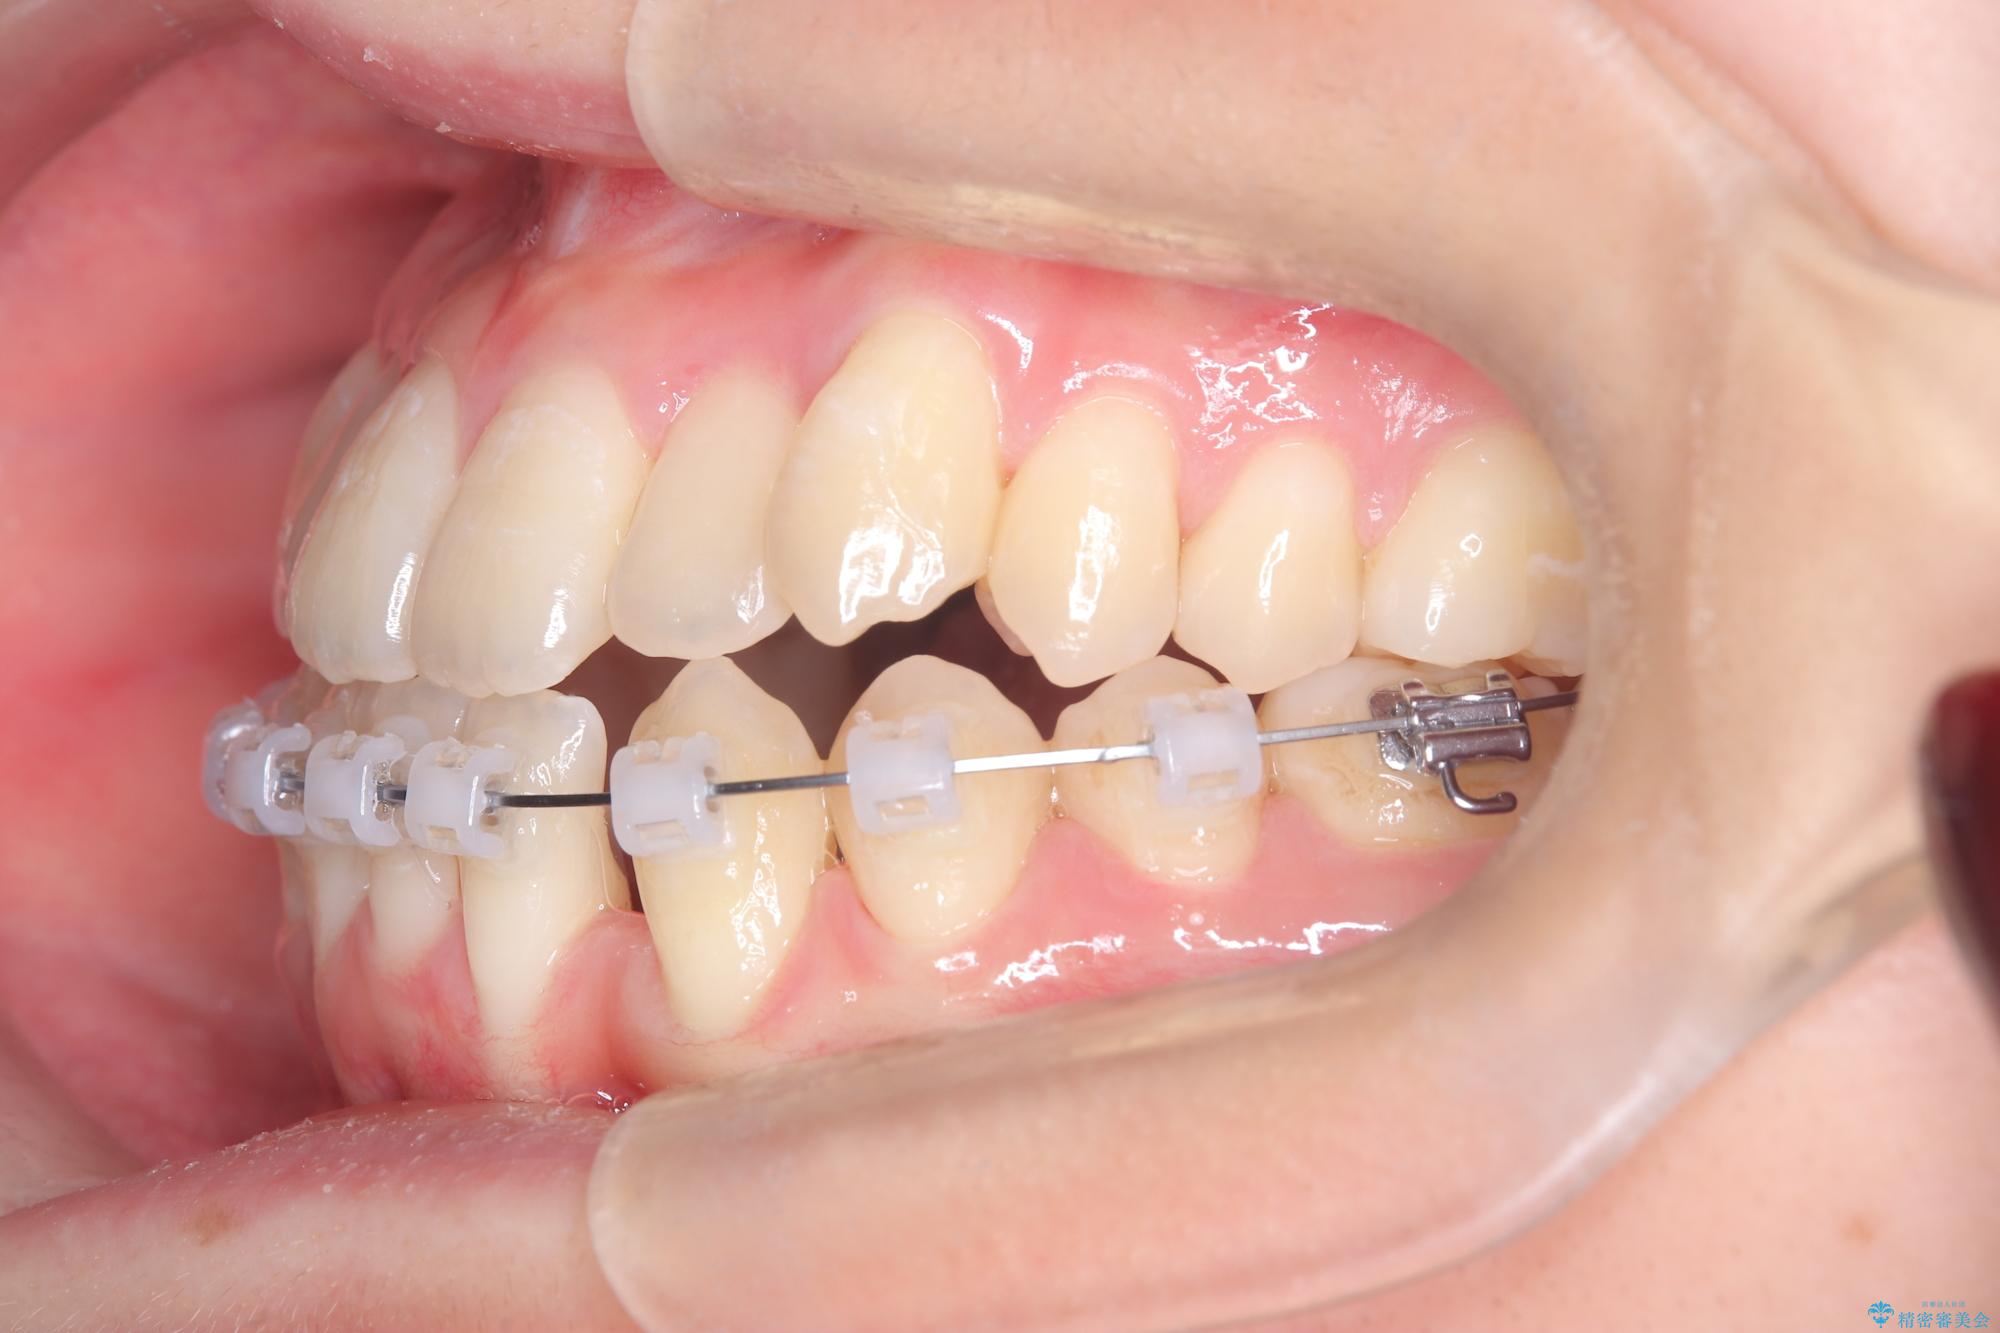

安全かつ確実に抜歯スペースを閉じ、咬み合わせを完成させるため、マウスピースから**ワイヤー矯正(マルチブラケット装置)**へ切り替えるリカバリープランを提案しました。

装置の変更と歯肉への配慮: ワイヤー矯正は歯の根(歯根)を平行に移動させる「歯体移動」を得意としています。本症例では、歯肉退縮を防ぐために、歯の傾きを精密にコントロールしながら抜歯スペースを閉じる必要がありました。ワイヤー装置を用いることで、インビザラインでは難しくなっていた三次元的な細かい調整を可能にしました。